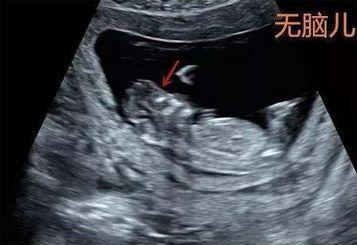

无脑儿:颅骨与脑组织缺失,偶见脑组织残基,常伴肾上腺发育不良及羊水过多。妊娠14周后,B超探查见不到圆形颅骨光环,头端有不规则“瘤结”;腹部触诊时,胎头较小;阴道检查时可触及凹凸不平的颅底部。